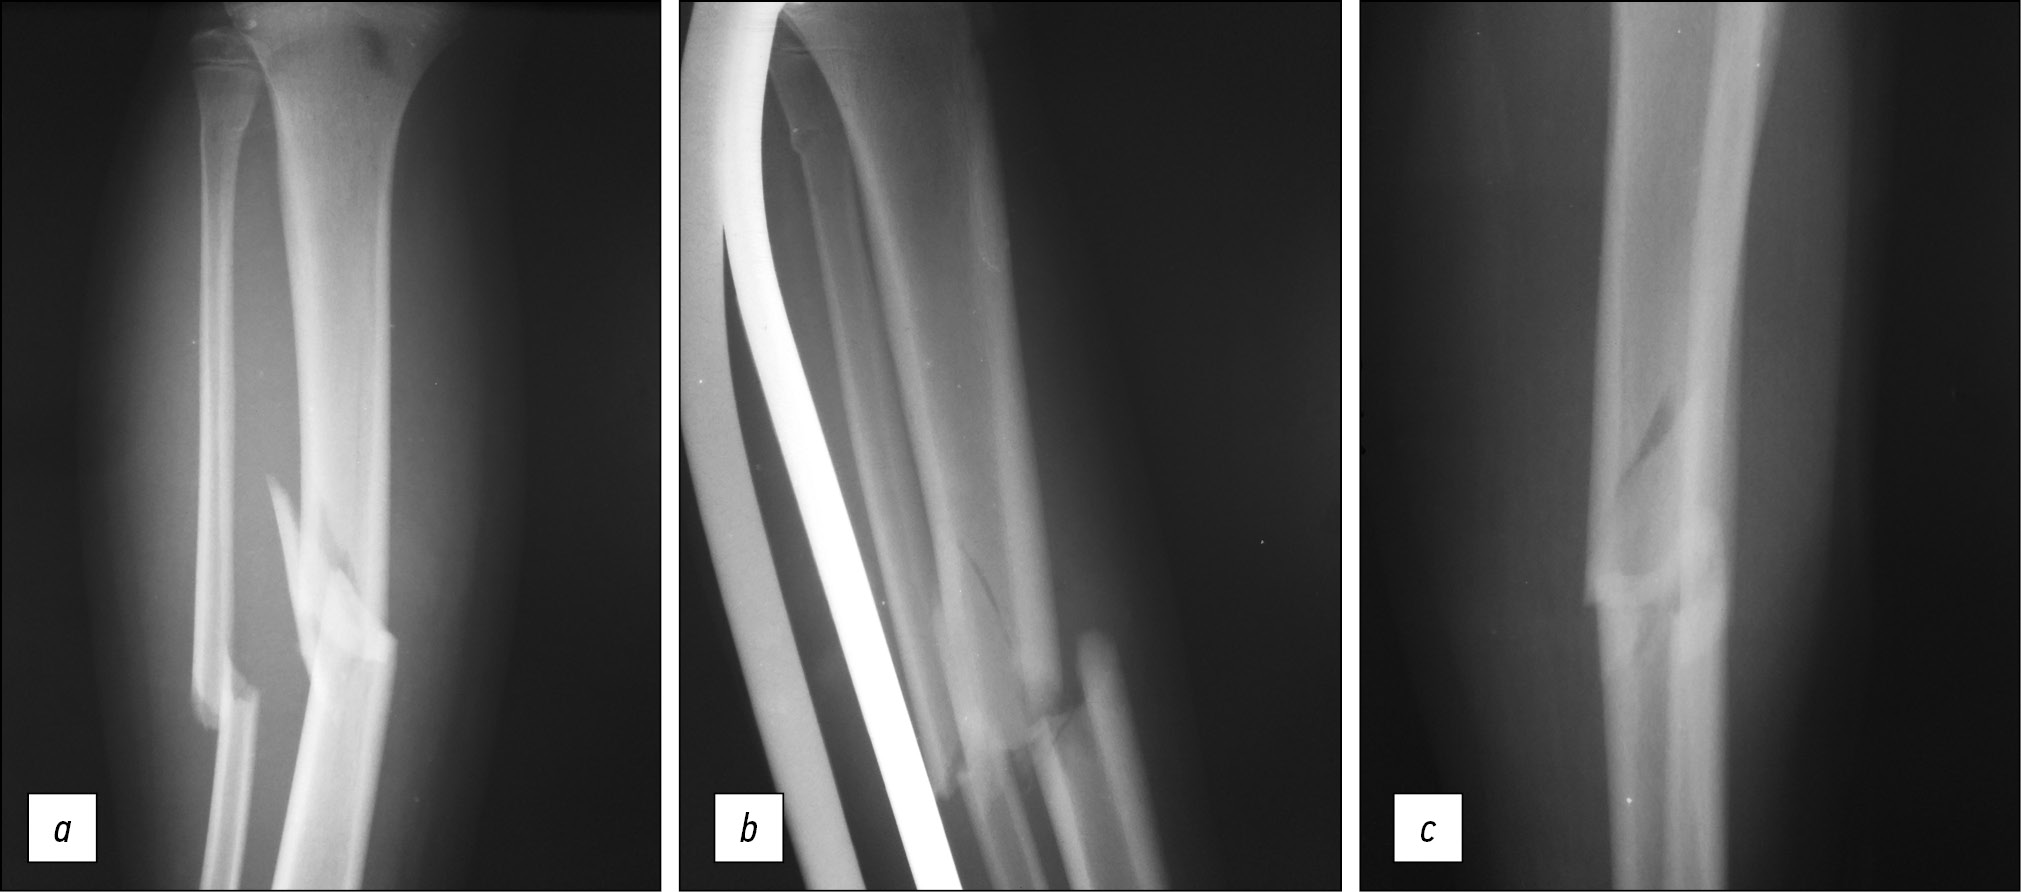

На рентгенограмме голени (рис. 1) в прямой проекции перелом большеберцовой кости на первый взгляд напоминает локальный ввиду имеющегося осколка, который в данной проекции имеет как будто клиновидную форму (основанием клина обращённый кнаружи, вершиной — кнутри), однако рентгенограмма голени в боковой проекции демонстрирует винтообразный характер перелома большеберцовой кости, что позволяет избежать ошибки, расценив данную травму как возникшую в результате локального воздействия травмирующего объекта.

Рис. 1. Винтообразно-оскольчатый перелом средней трети диафиза большеберцовой кости, косой перелом средней трети диафиза малоберцовой кости, поднадкостничный перелом верхней трети диафиза малоберцовой кости (субкапитальный перелом) со смещением отломков на рентгенограммах в прямой (а), боковой (b) и нестандартной косой (с) проекциях.

Fig. 1. X-ray of the right leg in direct projection. Screw-comminuted fracture of the middle third of the tibial shaft, transverse fracture of the middle third of the fibula shaft, subperiosteal fracture of the upper third of the fibula shaft (subcapital fracture) with displacement of fragments on radiographs in direct (a), lateral (b) and non-standard oblique (c) projections.